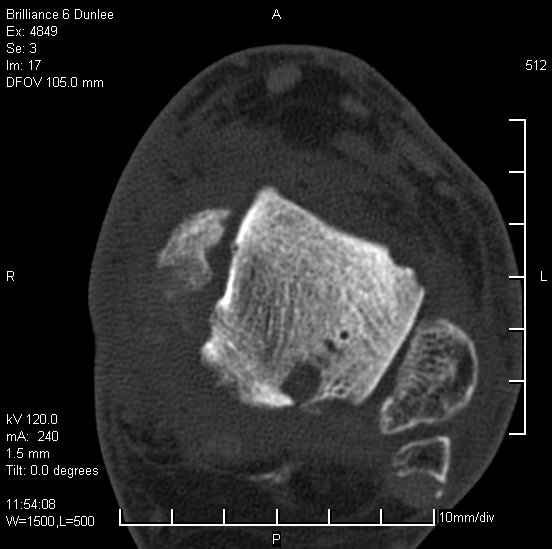

Асептический некроз таранной кости.

На лечении находится пациент 35 лет. Травма в сентябре 2008 г.- открытый вывих таранной кости

В день травмы ПХО, вправление вывиха, трансартикулярная фиксация. Рана зажила первично. С января нагрузка на конечность. С конца апреля- болевой синдром. На рентгенограммах и КТ признаки ас. некроза таранной кости, артроз подтаранного и голеностопного суставов.